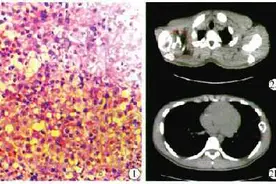

脊柱嗜酸性肉芽肿